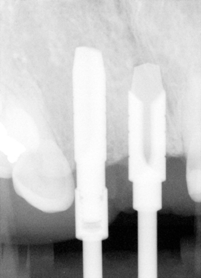

The adjusted stent fits well after raising the flap (Fig.14). Initial osteotomy is made using the stent. The osteotomy for #8 is located in the middle of the ridge labiolingually, whereas that for #7 is too lingual. Adjustment is made freehand. The final osteotomy is shown in Fig.15: 4.0 mm in diameter for #7 and 4.5 mm for #8. With direct vision (large exposure) and digital palpation, there is no perforation (not shown). There is concavity in the labial plate (arrowheads in Fig.15), which is corrected by connective tissue graft. The arrowhead in Fig.16 points to the suture that stabilizes the graft against the labial mucoperiosteal flap.

Fig.17 shows paralleling pins at 8 mm (trajectories are corrected sequentially, but not enough); Fig.18,19: reamers 4.0 mm at #7 and 3.5 mm at #8 at the depth of 11mm; Fig.20 reamers 4.0 mm at #7 (14 mm deep) and 4.5 mm at #8 (11 mm); Fig.21: Bicon implants: 4.0 x 11 mm at #7 and 4.5 x 8 mm at #8.